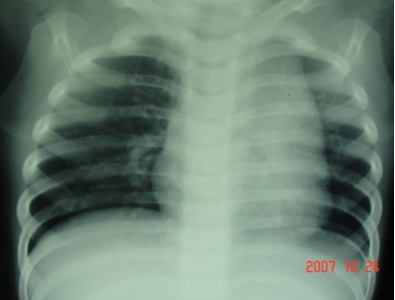

肺血正常

肺动脉瓣狭窄

右心缘饱满;肺动脉段凸出